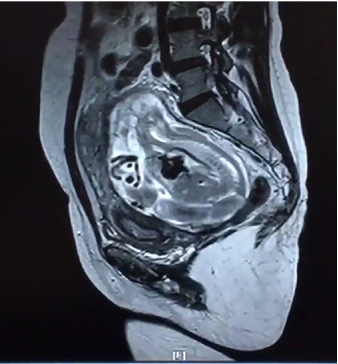

2月24日,我院产科、泌尿外科、麻醉手术科、胃肠外科、输血科等多学科合作成功救治一名腹腔妊娠特殊患者。这是我院多学科合作战胜疑难杂症的又一成功案例。近年来,作为三级甲等综合医院,华人色情 始终坚持以患者为中心,充分发挥综合医院的优势,积极探索研究,持续加强学科建设,不断拓展多学科合作的广度和深度,利用多学科合作为人民群众解决了很多疑难杂症,用实际行动巩固脱贫攻坚成果,助力乡村振兴,为维护人民群众的健康持续奋斗。